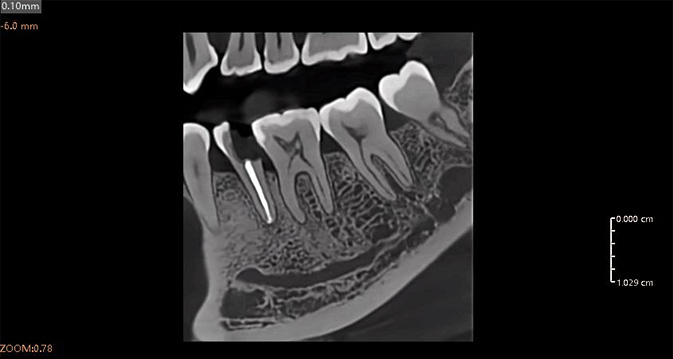

Análisis Endodóntico Impulsado por IA

El módulo de endodoncia de IA detecta y aísla automáticamente cada diente, proporcionando tres modos de visualización 3D: superficie, conducto radicular y transparencia. Esto permite una observación precisa de la morfología, el número y el detalle del conducto radicular, ayudando a los clínicos a realizar diagnósticos y mediciones precisas con facilidad.

Al-Powered: detección rápida y precisa de enfermedades

Precisión impulsada por IA: visualización óptima de las condiciones

Herramientas mejoradas para la comunicación con los pacientes

La herramienta de planificación impulsada por IA detecta automáticamente los dientes y el nervio alveolar inferior, proporcionando alertas de seguridad en tiempo real. Soporta medición automática, simulación de implantes y optimización de trayectoria, lo que permite una planificación de tratamiento rápida y precisa.